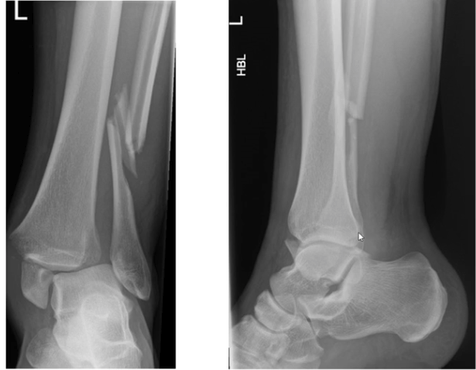

What is shown in this X-ray?

Weber’s A fracture